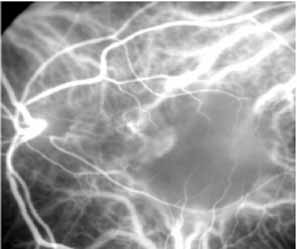

Flower revealed that feeder vessels (FVs) identified by dynamic ICG angiography, but not by FA, may be amenable to treatment with argon green laser.32 ICG angiography is then performed at regular intervals after treatment to determine the treatment response. A second laser treatment is administered if ICG angiography reveals a patent FV. A 40% success rate was found, initially, with a more recent report of 75% success.33 It appears that dynamic ICG angiography, especially high-speed ICG, detects smaller FVs and can therefore be used in treatment of these vessels. (Fig. 10)

Fig. 10 High-speed indocyanine green angiography image of a feeder vessel.